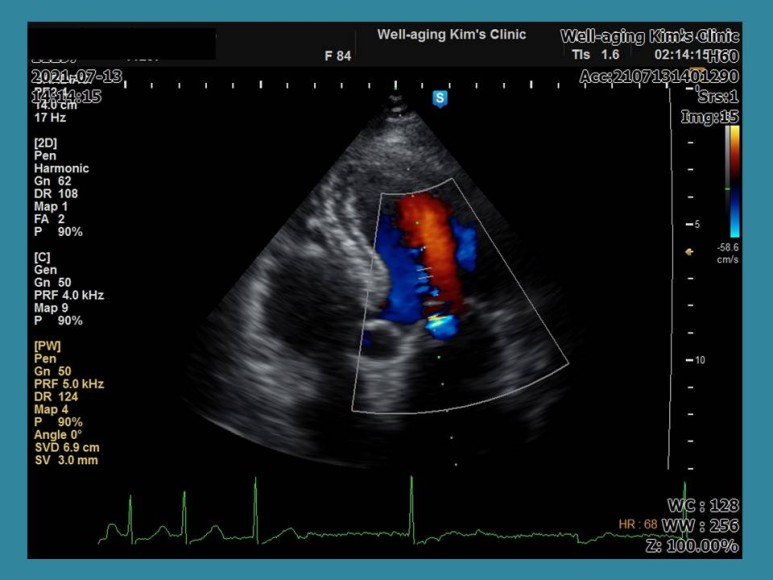

심장근육의 두께, 전체적인 심장의 크기, 판막의 기능, 그리고 다른 복부초음파와의 큰 차이는 심장의 혈역학적 상태를 평가하는 것이지만

좌심실에서 대동맥으로 나가는 혈류 속도 및 좌심방에서 좌심실로 들어갈 때의 혈류속도 심장의 조직 움직임 속도 등을 평가하고 이완기 심부전 등을 평가하는 것이

심장초음파검사가 다른 검사를 대체할 수 없는 가장 핵심적인 역할을 한다고 볼 수 있다.

판막 기능이 문제가 있을 때도 가벼운 상태인지 심한 상태인지를 감별하는 것도 심장 초음파 검사에서만 가능하다.